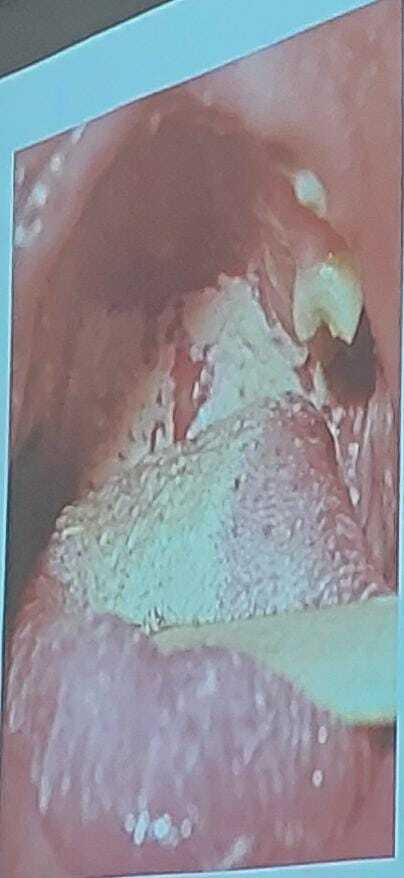

CANDIDIASIS ORAL

Características

A

• Px sanos: RN y adultos mayores (❗OJO: ox adolescentes puede ser foco rojo de inmunosupresión).

• Aspecto característico en mucosas: aspecto blanquesino